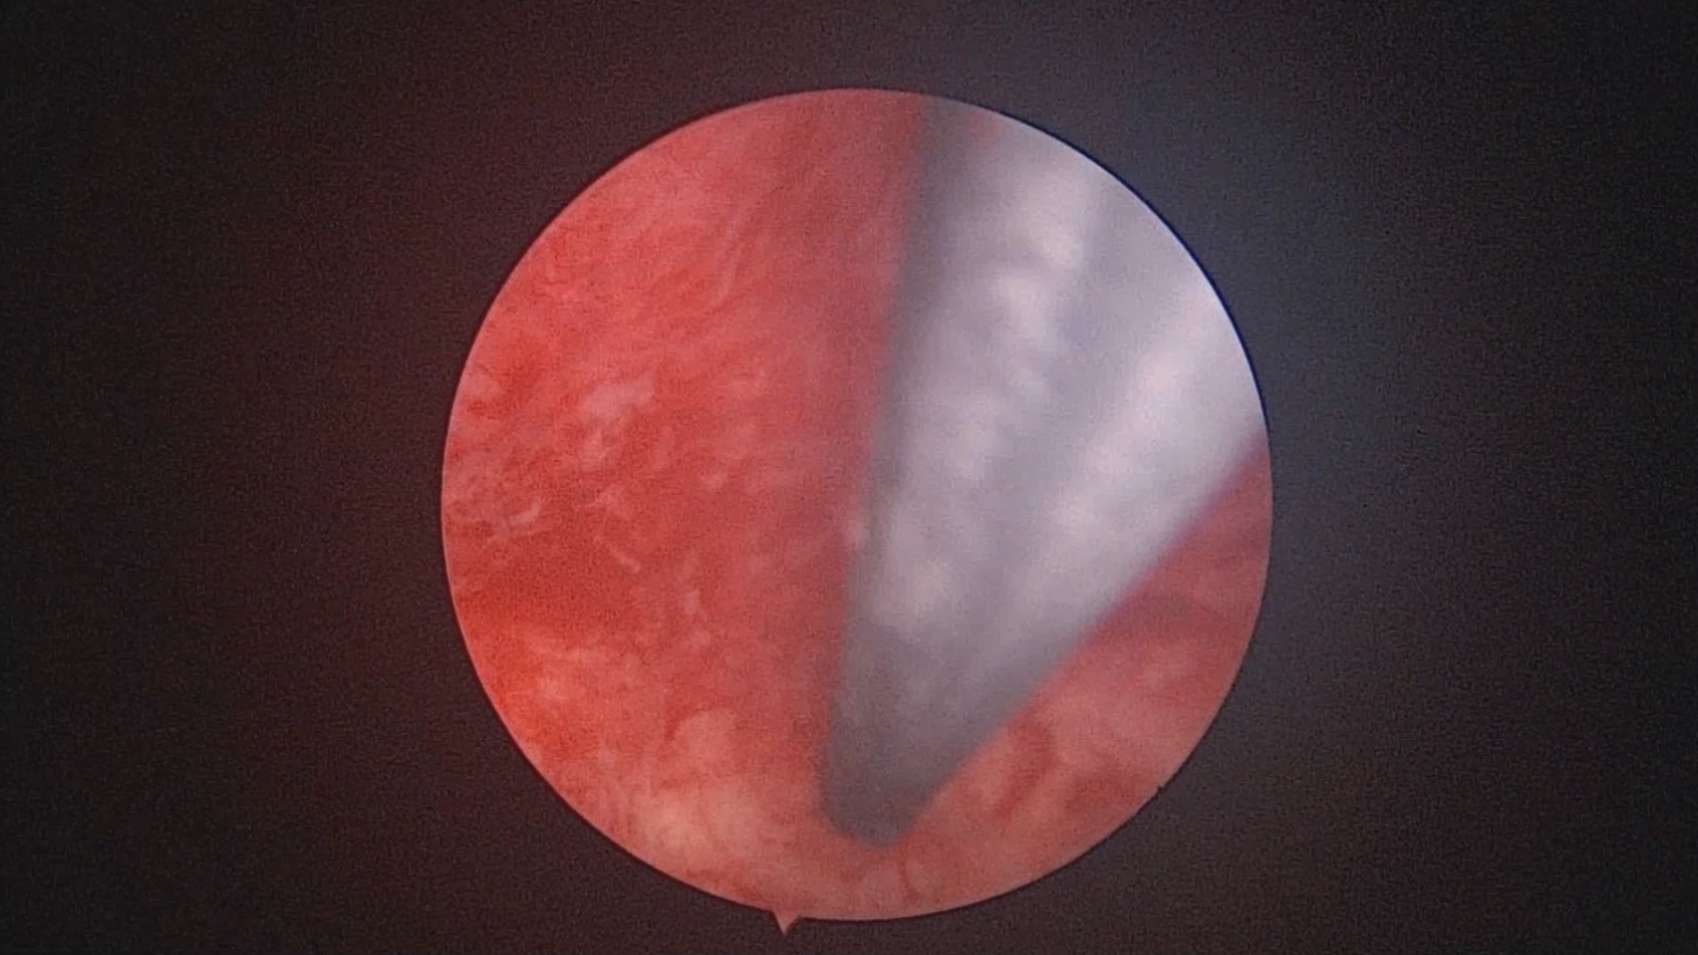

患者37岁,G3P1,剖宫产1次。子宫腺肌症合并子宫肌瘤6年,月经量增多1年。B超子宫前位,6.6cm*5.5cm*5.8cm大小,子宫后壁肌瘤直径6cm。2024年12月宫腔镜探查,宫深9cm,放置曼月乐并固定。用曼月乐尾丝在环横臂中间套扎形成线圈,异物钳夹持线圈挂到不锈钢挂钩里,将环固定于宫底,患者及家属拒绝内膜送病检。术后多次复查B超,曼月乐位置正常,最后一次环顶端距宫底1.2cm。